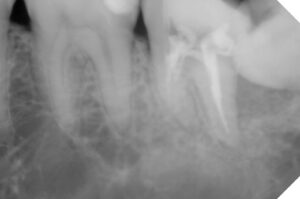

同年2/19 最短で根の処置から被せるまでこぎ着け

E-max set 自費:75000円

仮歯との違い と セラミックと金属の見た目

口腔内写真で明らかに違いが判るのは

保険で銀歯→ 自費で白い歯→

レントゲンでは神経の詰め物の状態の違い→

歯根の崩壊度は経時的なもの?→